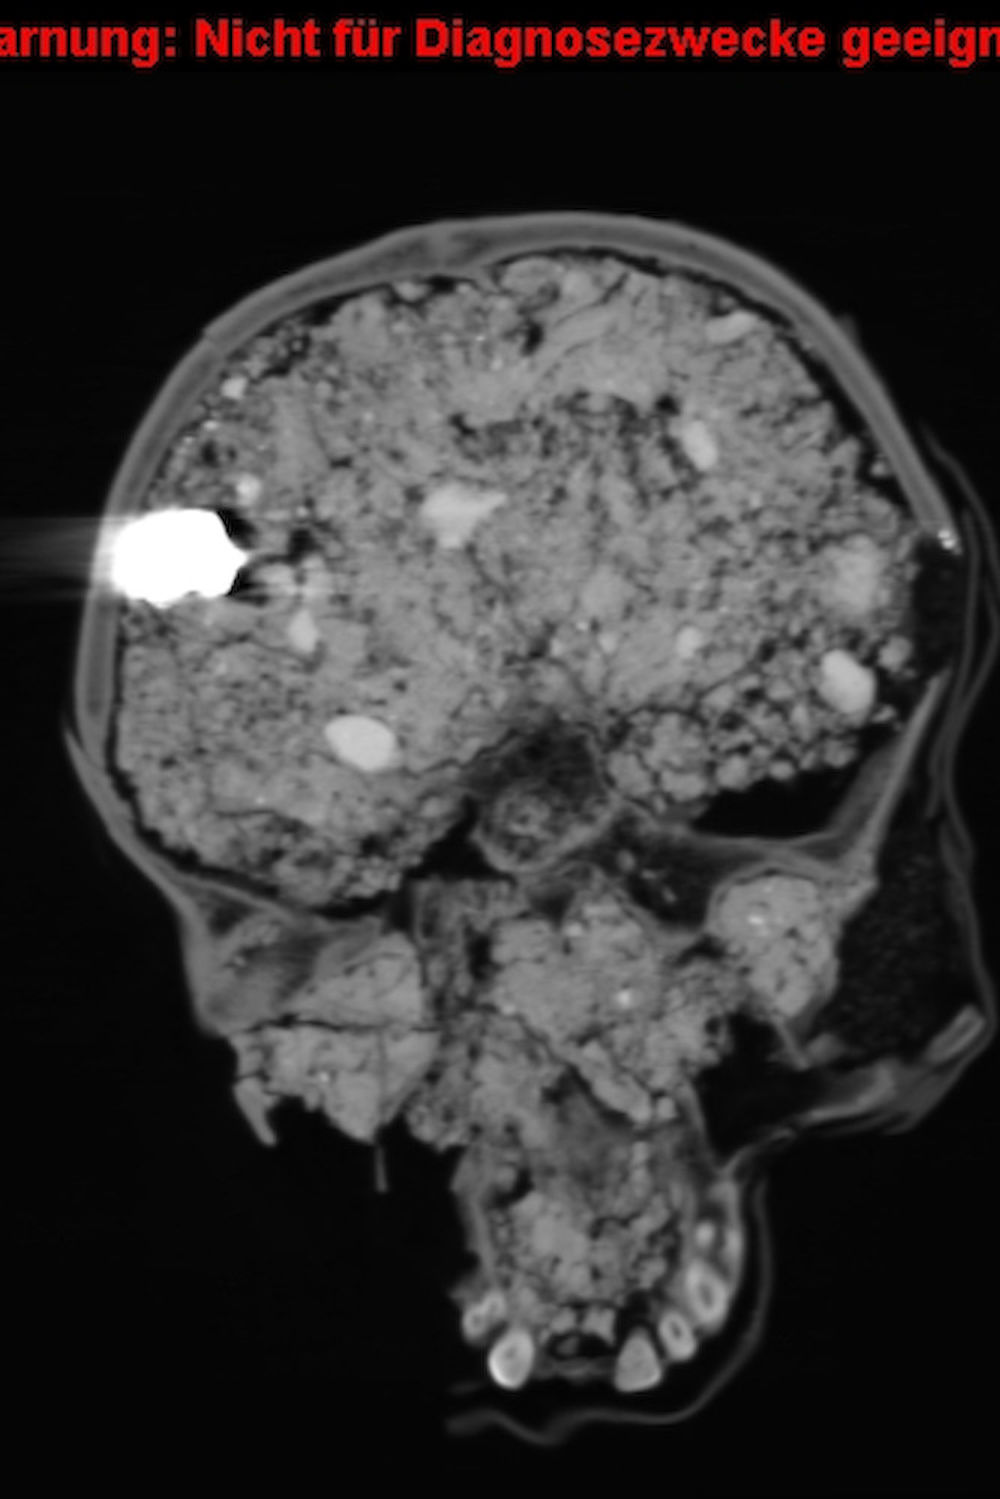

Silvio Brandt erklärt, was man anhand der Bilder erkennen kann (Slideshow):

„Es ging darum, Verletzungsmuster zu klären“, sagt der Oberarzt. 16 Schädel sind dafür von 2012 bis 2013 im CT untersucht worden. Dabei fand er heraus, dass einige der Männer hinterrücks erschossen wurden. „Die Befunde weisen Schussverletzungen von oben leicht nach unten führend auf, was darauf schließen lässt, dass einige der Soldaten zu Fuß vor Berittenen davongelaufen sind und von hinten getroffen wurden“, erklärt Brandt und zeigt dabei auf die CT-Aufnahmen auf dem Bildschirm in seinem kleinen, abgedunkelten Büro. Eine kurze Bewegung mit der Maus und die Aufnahmen eines Schädels laufen ab wie ein Film, so dass sich auch der Schussverlauf gut nachvollziehen lässt.

Außerdem lässt sich der Betrachtungswinkel der Aufnahme so verändern, dass der Knochen in 360-Grad-Perspektive betrachtet werden kann. Aufgrund der Untersuchungsmethode konnte auch das Sediment der Fundstelle in den Schädeln bleiben. „Das sind die lilafarbenen Flecken auf den Aufnahmen“, sagt Brandt. In einigen Schädeln steckten sogar noch die Bleikugeln – ganz oder zersplittert. Das lasse Rückschlüsse auf die Entfernung der Schützen zu, so Brandt. Simpel gesagt: Je näher man der Waffe war, desto mehr Durchschlagskraft hatte sie. Geschossen wurde damals, vor fast 400 Jahren, hauptsächlich mit Musketen und Pistolen.

Auch im Nachhinein sind noch Frakturen an den Knochen entstanden. Das Gelände des damaligen Schlachtfeldes, das von der alten Handelsstraße Via Regia und heutigen Bundesstraße B87 durchschnitten wird, wurde bis heute als Feld genutzt und ist teilweise bebaut. Schwere Landwirtschafts- und Baugeräte haben demnach ebenfalls Spuren hinterlassen, denn das Grab lag relativ nah an der Oberfläche. „Man kann anhand der Aufnahmen auch sehen, welche Verletzungen jünger sind und diese als Todesursachen ausschließen“, sagt Brandt.